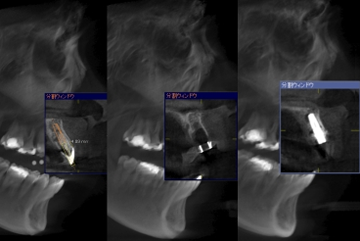

インプラントを行う際に、歯科用CTで上顎や下顎の骨の状態や、骨の中を神経や血管がどのように走っているのか、周囲の組織の状況を確認することはとても重要なステップです。

顎の骨の厚みや、神経の通っている位置は一人ひとり違います。歯科医師は3次元のCT画像を見ることで綿密な治療計画を立てることができます。

絶対に必須とまでは言えないにしろ、より安全でより正確な治療を受けるためには、歯科用CTを置いている歯科医療機関を選ぶ方が賢明です。

予後の良い治療のためには、歯科医師の経験の蓄積に加えて、歯科用CTによる詳細な画像診断を行い、患者さんが納得できるまでインフォームドコンセントを実施しながら、治療を進めていくことが大切です。